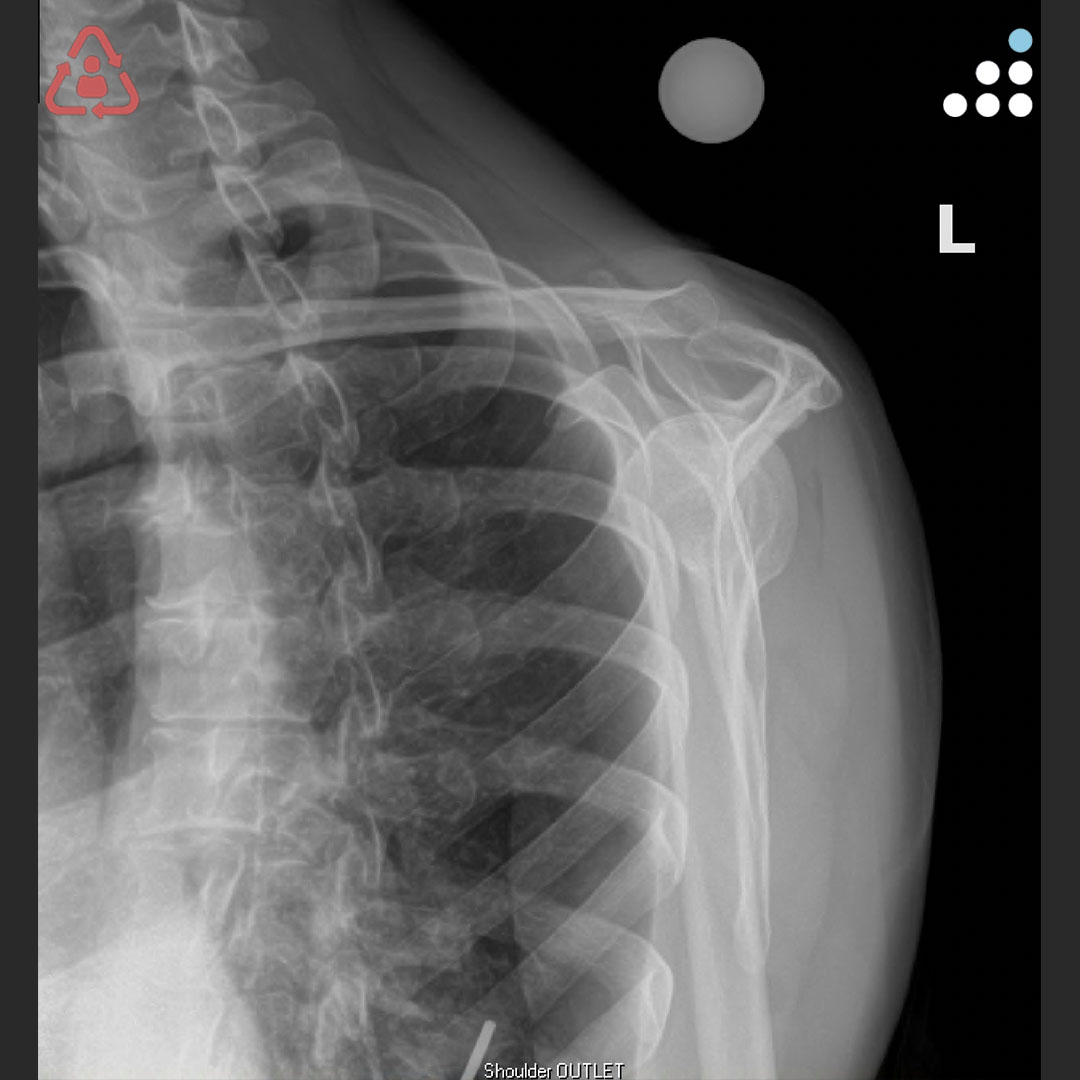

@orthobullets @KPSCALnews @rkh_md @DrMarecek @DeformityDoc @jamesablairMD @FractureDoc @stevemchale @traumaticum @DrFraneNicholas I am concerned about the +Fleck/flake sign. Get MRI or ultrasound to rule out a triceps rupture. If torn, I would perform ORIF and Triceps repair, after restoring the underlying metabolic issues. If the triceps is not torn, then would treat non-operatively.